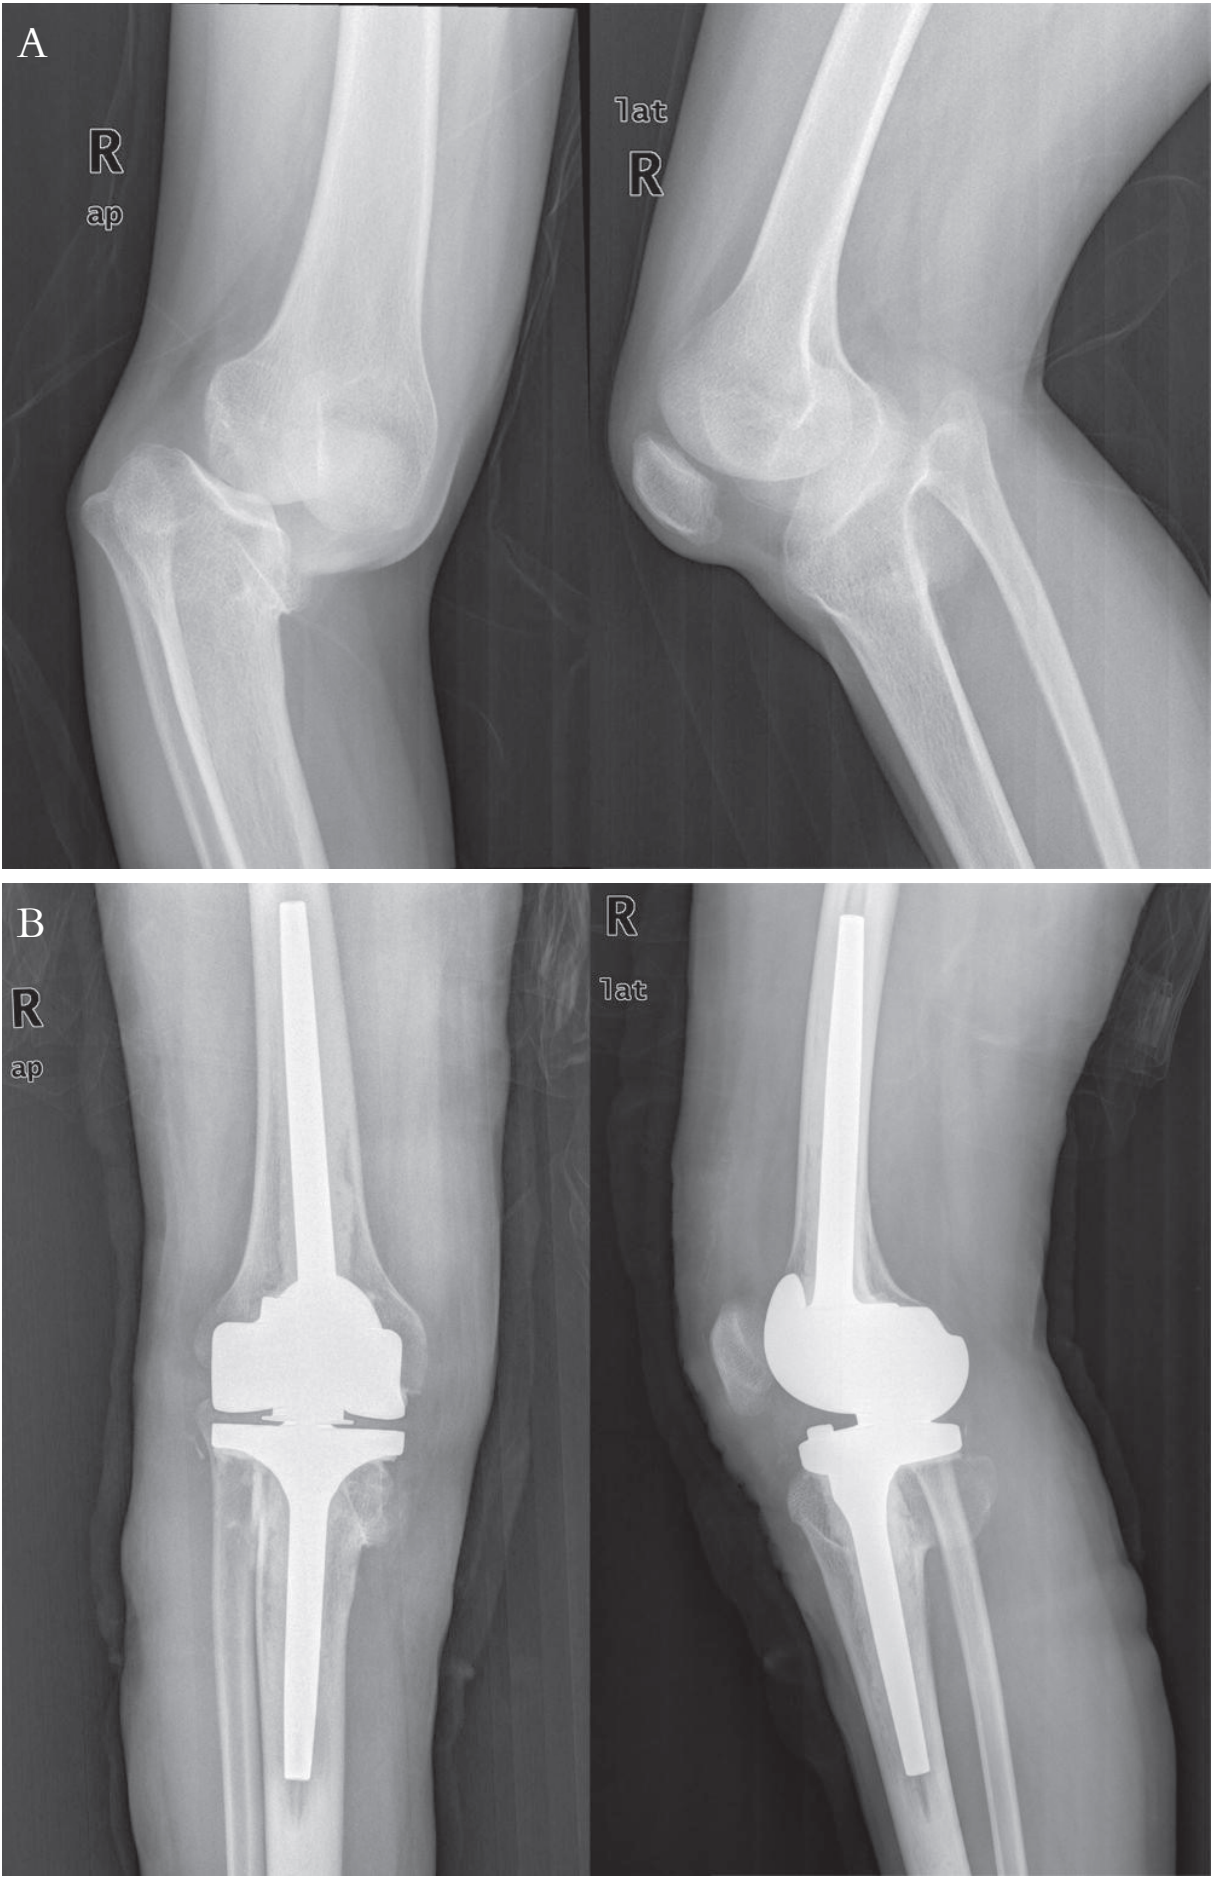

旋转铰链型假体置换术前后X线片

注:A:术前×线片;B:术后×线片。

旋转绞链膝关节假体在绞链膝关节基础上,使股骨假体连接在胫骨假体突起的旋转轴上,并依靠衬垫将股骨假体与胫骨假体连成一体。股骨假体相对胫骨衬垫不但有屈曲活动,还有一定的旋转运动。假体有良好的内在稳定性,不依赖膝关节的韧带和软组织,不需要进行软组织平衡,术中可切除内、外侧副韧带。股骨和胫骨假体均为抗旋转设计、有长柄分散假体界面应力,固定可靠。假体轴心距胫骨关节面的最低点约22.5mm,运动轴置于生理区域,较少发生髌股关节并发症。

旋转绞链膝关节假体主要应用在严重的膝内外翻畸形、严重膝关节屈曲挛缩畸形、强直膝、有严重骨缺损或侧副韧带功能缺陷的膝关节翻修病例。特别适用于内、外侧副韧带均受损或无法平衡屈伸间隙的患者。尽管旋转绞链膝增加了旋转功能,但仍是限制型假体,置换后假体与骨连接界面承受应力更大,再次翻修很困难。